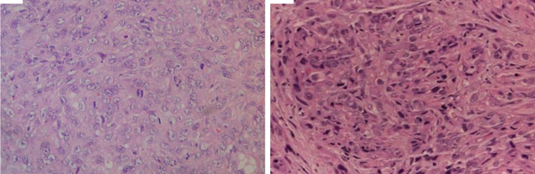

Παθολογοανατομική εξέταση δερματικής βλάβης. Χρώση αιματοξυλίνης-εοσίνης που δείχνει φωλιές μονόμορφων καρκινικών κυττάρων με μεγάλη ατυπία, βαθυχρωματικούς πυρήνες και ενεργούς μιτωτικούς δείκτες χωρίς εμφανή μελανίνη (Ευγενική παραχώρηση Dr. V. Penopoulos)